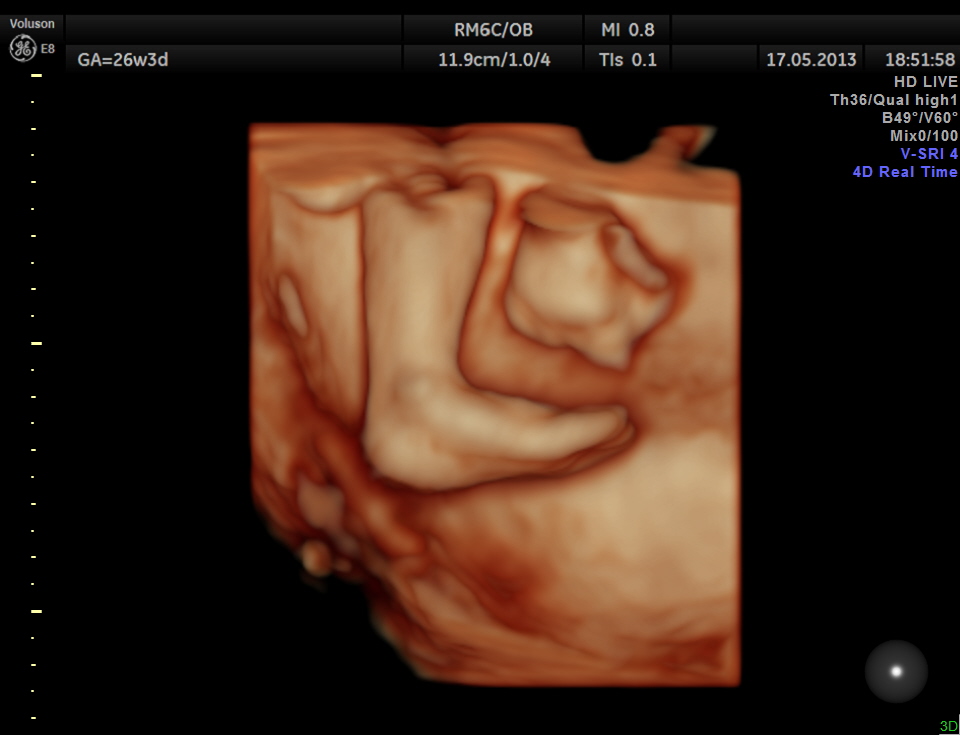

The limbs are shown below.